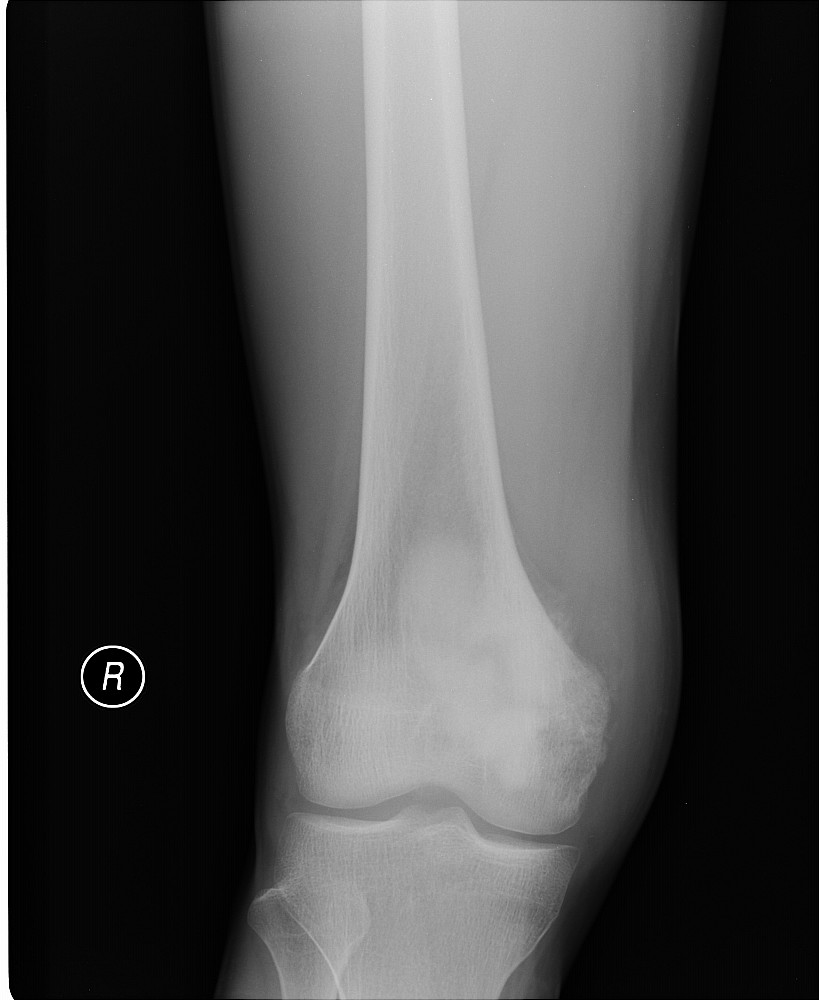

以下是引用黑白光影在2009-3-13 13:00:00的发言:[br]考虑右股骨远端内侧缘絮样骨质密度影,髁上可见骨膜反应,相应侧软组织肿胀,考虑成骨肉瘤可能。

以下是引用guo430726在2009-3-13 13:50:00的发言:[br]考虑右股骨远端内侧缘絮样骨质密度影,髁上可见骨膜反应,相应侧软组织肿胀,考虑成骨肉瘤可能。[br]支持!